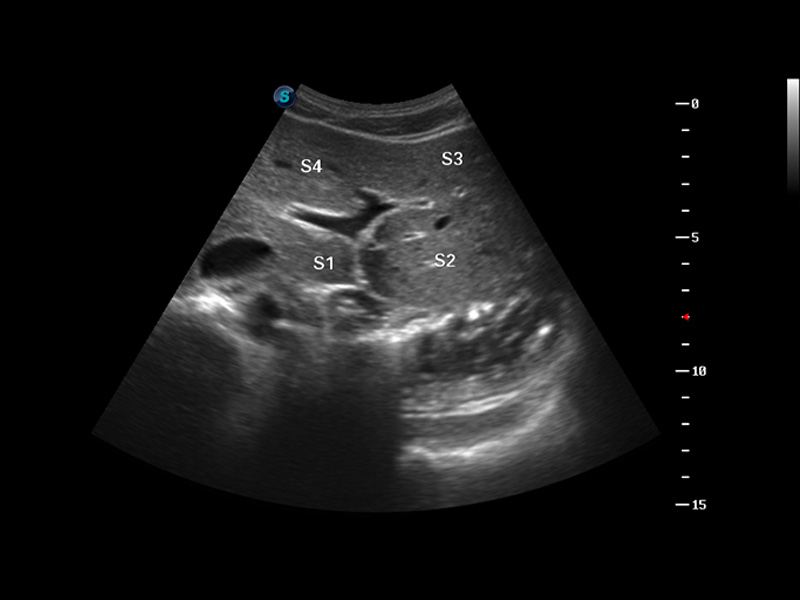

谐波成像

实时宽景成像

空间复合成像

3D/4D成像